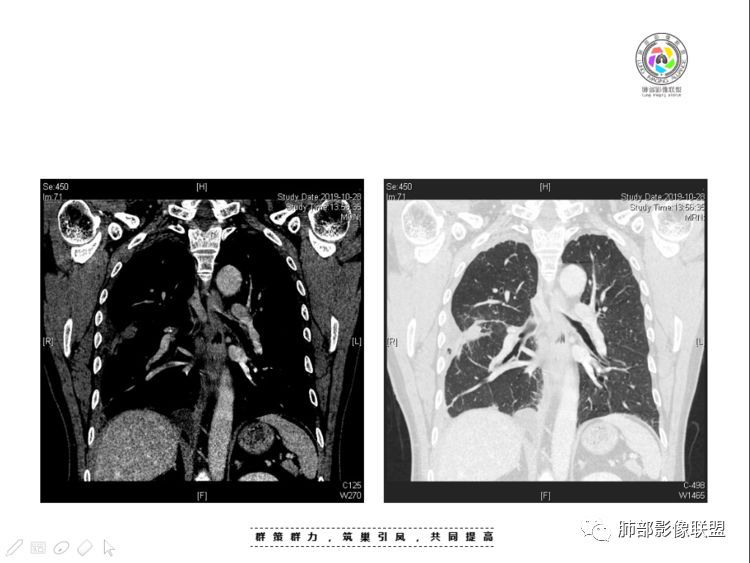

本例纵隔与肺内两处病变,回顾总结分析:

1、右肺内病灶,病灶呈结节样,边缘欠规则,局部膨隆,叶间裂胸膜牵拉凹陷,再看相应支气管腔堵塞截断,临床资料胸水中查到癌细胞,均提示病灶倾向恶性,腺癌的病理意见与之相吻合。

黄勇老师总结,腺癌如果与胸膜、叶间裂紧贴或伴胸膜凹陷,胸膜、叶间裂多发结节,应当高度怀疑腺癌转移。

2、前纵隔内病灶囊实性混杂密度病灶,囊性病灶主要位于右侧,张力较高,有分隔影,囊壁右侧缘光整,病灶左侧实性部分边界不清明显强化,病灶肺瘤交界面大部分边界清楚,部分模糊。

前纵隔肿块伴囊变坏死常见以有胸腺瘤、胸腺癌、淋巴瘤和生殖细胞肿瘤。

纵隔内病灶不符合肺癌转移途径,且纵隔内单发的囊实性转移罕见。淋巴瘤无论是分布、形态、密度、还是强化方式度不符合。

胸腺瘤/胸腺癌:病灶内那么大的囊,常规考虑B型以上胸腺瘤,囊内有分隔影,病灶周围脂肪间隙模糊,常规考虑侵袭性胸腺瘤或胸腺癌,若侵袭性胸腺瘤,常侵犯胸膜、心包,很少累及肺。胸腺癌易侵犯胸膜、肺并纵隔淋巴结及远处转移。但肺内腺癌形态更符合原发灶。胸膜及叶间裂转移则即可来自肺,也可来自胸腺癌。

尽管前纵隔病灶缺乏相关病理资料,但是小编还是认为肺内与纵隔病灶以二元论解释。只是肺内恶性病灶引发的胸膜改变可能会影响我们对纵隔病灶的判断。